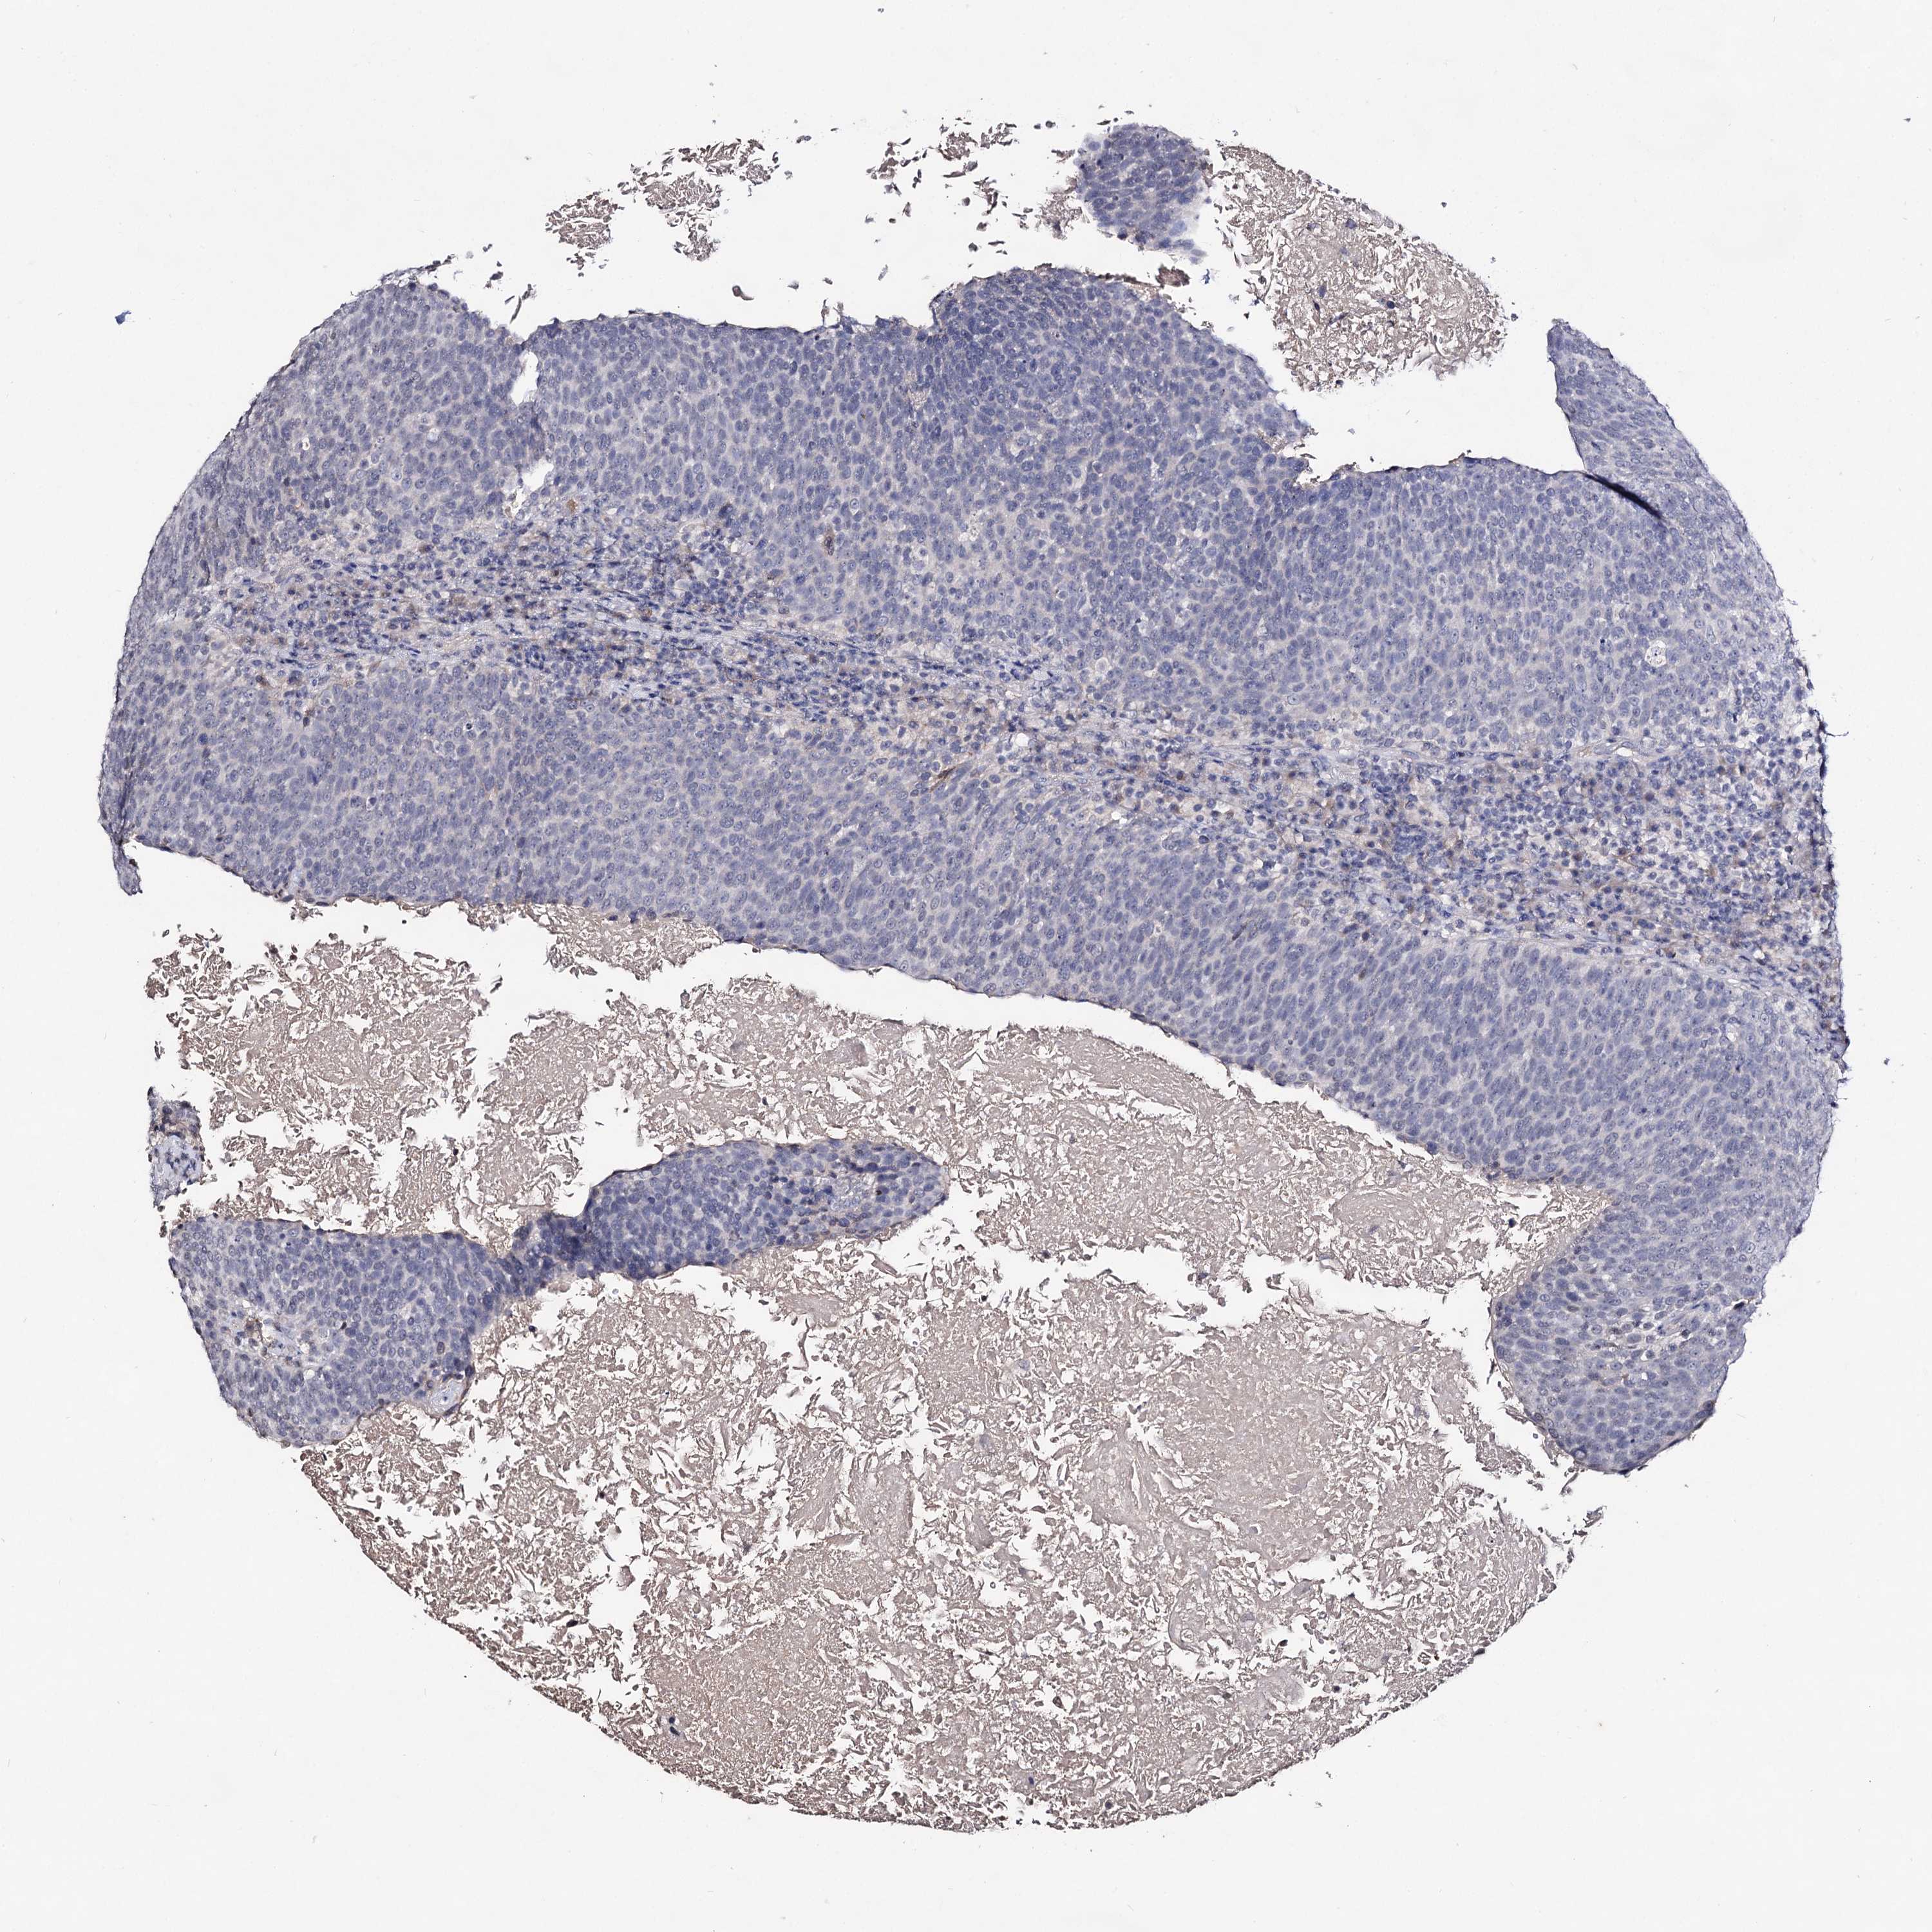

HEAD AND NECK CANCER - Protein expressioni

A mouse-over function shows sample information and annotation data. Click on an image to view it in a full screen mode. Samples can be filtered based on level of antibody staining by selecting one or several of the following categories: high, medium, low and not detected. The assay and annotation is described here.

Antibody stainingi

Antibody staining in the annotated cell types in the current human tissue is reported as not detected, low, medium, or high, based on conventional immunohistochemistry profiling in selected tissues. This score is based on the combination of the staining intensity and fraction of stained cells.

Each image is clickable and will lead to virtual microscopy that enables deeper exploration of all samples and also displays staining intensity scores, fraction scores and subcellular localization as well as patient and tissue information for each sample.

Antibody HPA024299

Antibody CAB033821

Antibody CAB037333

Staining

High

Medium

Low

Not detected

Intensity

Strong

Moderate

Weak

Negative

Quantity

>75%

75%-25%

<25%

None

Location

Nuclear

Cytoplasmic/membranous

Cytoplasmic/membranous,nuclear

Squamous cell carcinoma, NOS

Squamous cell carcinoma, metastatic, NOS

Adenocarcinoma, NOS

Adenocarcinoma, metastatic, NOS